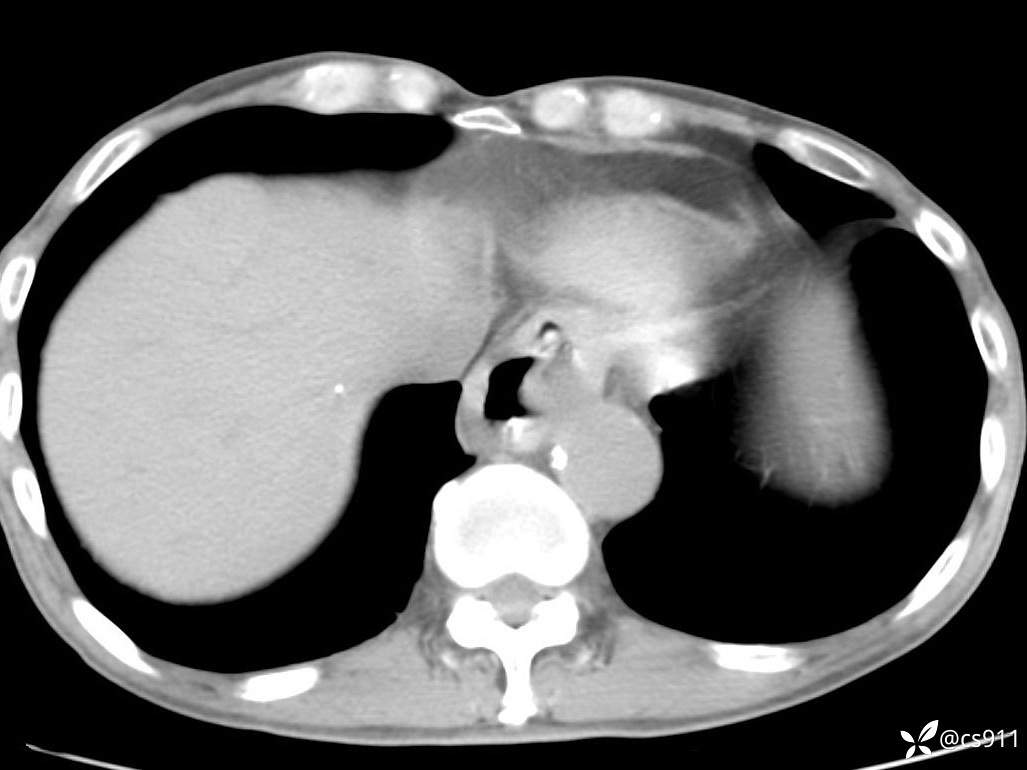

急腹症之急诊CT,原因?答案公布

男,77岁,腹痛、腹胀伴恶心呕吐1天。呕吐胃内容物,非喷射性呕吐,有咖啡色样胃内容物,诉有胃穿孔病史。查体:全腹平,下腹部压痛,全腹无反跳痛,叩诊呈浊音,移动性浊音阴性,肠鸣音减弱,1-2次/分。肛检:直肠未扪及明显肿物,可触及大量粪块。

血淀粉酶(AMY) HH 1859 U/L 35-135

癌胚抗原(CEA) H 27.44 ng/ml 0-5